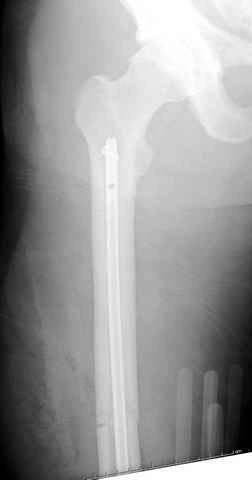

03.14.2005

больному 42, автоавария, политравма, открытая черепномозговая травма, безсознании, открытый перелом бедра, размозжение мягких тканей, дефект кожи на передней поверхности бедра около 13 см2 от ожога, компартмент синдром.

По поводу открытого перелома больной ургентно взят на ретроградное интрамедулярное штифтование, после рутинного дебрайдмента и фасциотомии на бедре и на голени.

перелом бедра

постоперационные